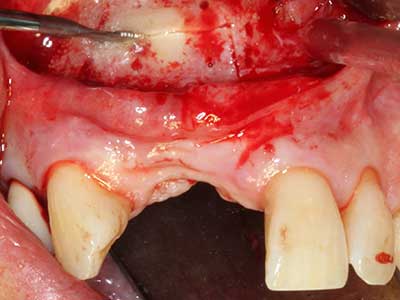

Quando le procedure chirurgiche vengono eseguite sull'osso nelle immediate vicinanze di strutture sensibili, come vasi sanguigni o nervi, gli strumenti rotanti pongono un rischio significativo di lesione iatrogena. I dispositivi piezoelettrici possono essere utili per la preparazione delle coperture ossee e la rimozione del tessuto duro in prossimità dei nervi, in particolare per la loro esposizione dopo una lesione iatrogena, ma anche durante la lateralizzazione dei nervi per le procedure di resezione e ricostruzione o il posizionamento di impianti (figg. 17-20). Il contatto leggero tra puntina piezoelettrica e nervo non causa generalmente danni, ma se si procede senza prestare attenzione con movimenti a sega o raccordi con residui di substrati ossei possono verificarsi danni al nervo temporanei o anche permanenti. Il rischio di danno, tuttavia, è considerato sostanzialmente inferiore al rischio presente utilizzando seghe o frese (Pereira, Gealh et al. 2014).